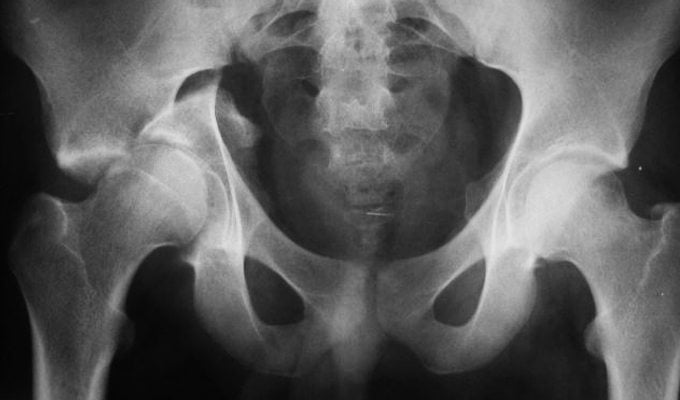

Приобретенный вывих тазобедренного сустава у взрослых имеет ярко выраженные симптомы, спутать которые с чем-либо еще невозможно. Поэтому патологию диагностируют без дополнительных методов исследования. Чтобы исключить переломы бедренной или тазовых костей, человеку делают рентгенографию ТБС в двух проекциях. Если у врачей есть сомнения в диагнозе, они могут назначить МРТ.

Чтобы убедиться в том, что головка бедренной кости встала на место, пациенту делают рентгенографию. Только после этого больному накладывают гипс.